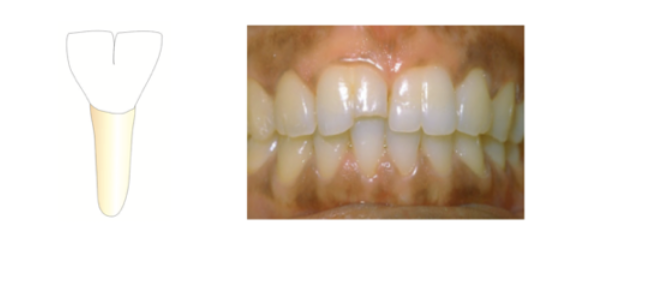

Fusion

2 buds merge into one tooth

* more common in primary teeth

* only anterior teeth

* count as 1 tooth